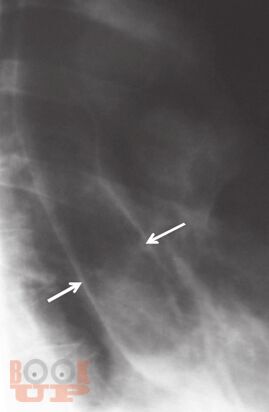

В основу издания положено собрание избранных клинических разборов, регулярно проводимых в ЦНИИ гастроэнтерологии. Многие из приведенных наблюдений являются уникальными, представляя собой либо клинический раритет, либо описание необычного течения давно известного заболевания, либо недавно описанное новое заболевание, прижизненный диагноз которого стал возможным благодаря внедрению новейших диагностических технологий. Особое внимание уделено и уникальным коррекционным вмешательствам.